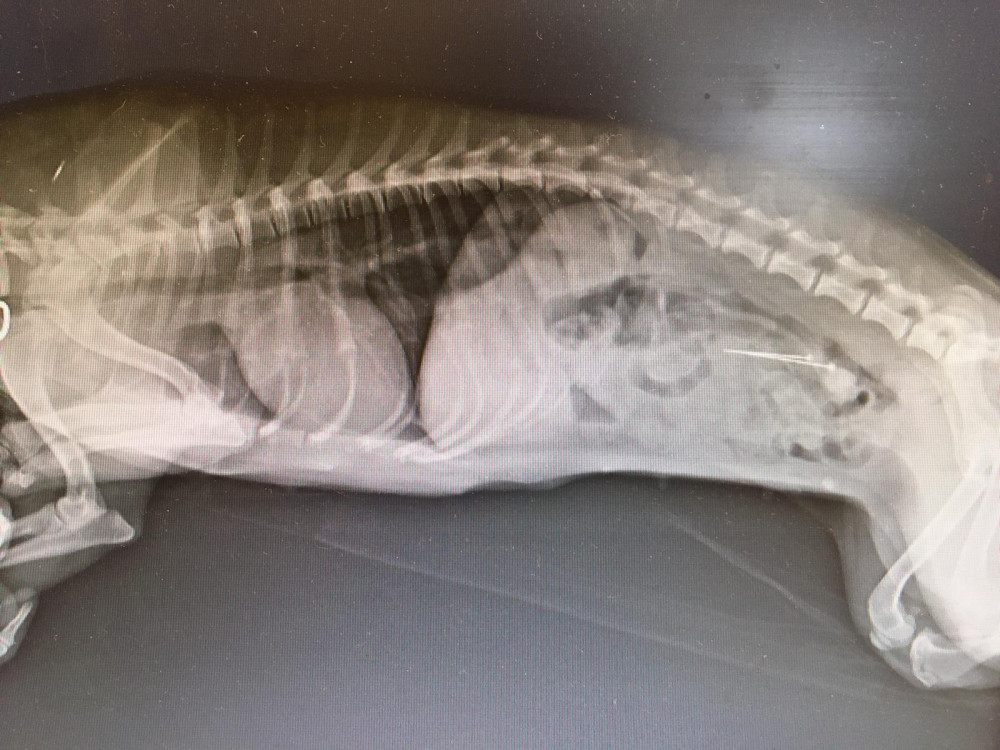

Nález špendlíků v trávicí soustavě psa